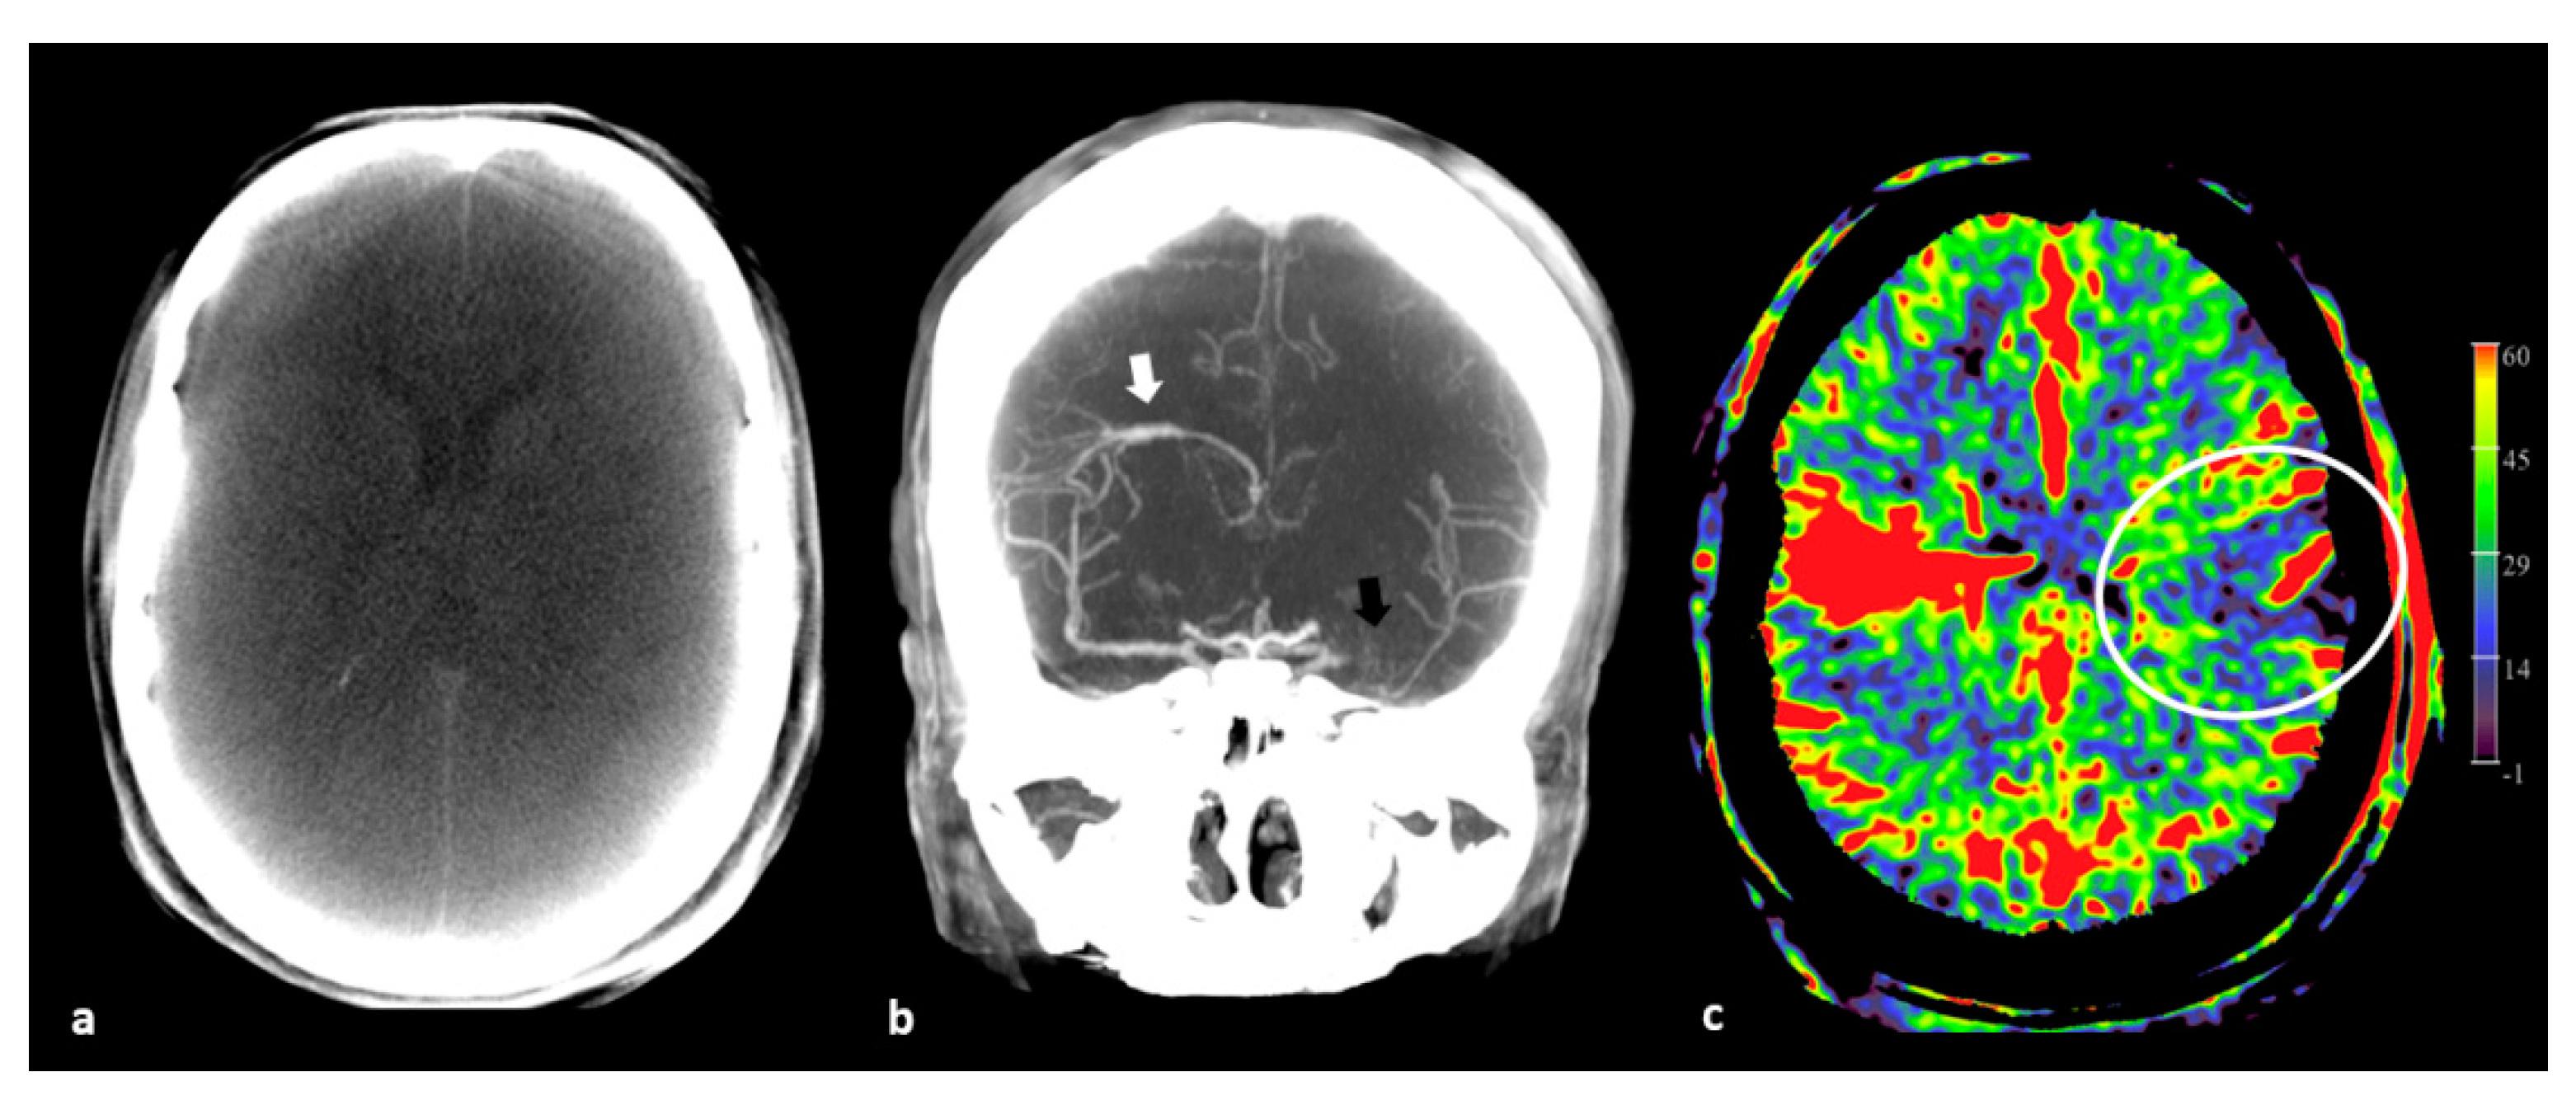

The angiographic perfusion imaging can be performed by both intra-arterial contrast injection (selective or by pigtail catheter in the ascending aorta), and intravenous contrast injection. Furthermore, it is possible to use the non-contrast “mask” run and the contrast-enhanced “fill” run for rendering multiplanar reformations to visualize the brain parenchyma and vascular structures. In Figure 1 the mask, fill, and PBV mapping are il-lustrated.

Figure 1.

Three available maps by FD PBV imaging. (a) Axial maximum intensity projection (MIP) reformation of PBV mask run in an acute ischemic stroke (AIS) patient demonstrates no obvious signs of infarct. However, the image quality is rather low. (b) Coronal fill run MIP image in another AIS patient shows no filling of the left middle cerebral artery (MCA, black arrow) M1-segment. Collateral filling post-occlusion is nicely demonstrated. As an incidental finding, a developmental venous anomaly (DVA, white arrow) is noted. (c) A PBV axial MIP reformation of the same patient of (b) (at the level of the DVA) displays a territorial low PBV area (ellipsoid), corresponding with the perfusion deficit area caused by the MCA M1-segment occlusion.